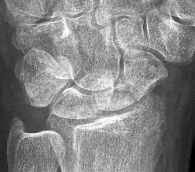

Question 44:

A 24-year-old man sustains a proximal pole scaphoid fracture after a fall on an outstretched hand. He is counseled regarding the high risk of nonunion and avascular necrosis associated with this specific fracture pattern. Which of the following accurately describes the primary blood supply to the proximal pole of the scaphoid?

Options:

- Retrograde blood flow from the dorsal carpal branch of the radial artery

- Antegrade blood flow from the superficial palmar arch

- Direct branches from the anterior interosseous artery

- Retrograde blood flow from the ulnar artery via the deep palmar arch

- Antegrade blood flow from the volar carpal branch of the radial artery

Correct Answer: Retrograde blood flow from the dorsal carpal branch of the radial artery

Explanation:

The scaphoid receives its primary blood supply from the dorsal carpal branch of the radial artery, which enters the bone distally and provides retrograde blood flow to the proximal pole. This retrograde supply makes proximal pole fractures particularly vulnerable to avascular necrosis and nonunion.

Question 65:

A 24-year-old man falls onto an outstretched hand and sustains an acute, minimally displaced fracture of the proximal pole of the scaphoid. Because of the specific vascular anatomy of the scaphoid, which of the following is the most widely recommended treatment for this injury?

- Short arm thumb spica cast for 6 weeks

- Long arm thumb spica cast for 12 weeks

- Percutaneous or open screw fixation

- Proximal row carpectomy

- Scaphoid excision and four-corner fusion

Correct Answer: Percutaneous or open screw fixation

The blood supply to the scaphoid enters distally via branches of the radial artery and flows retrograde to the proximal pole. Because of this tenuous vascular supply, proximal pole fractures have a very high rate of nonunion and avascular necrosis. Operative fixation (percutaneous or open) is recommended even for non-displaced proximal pole fractures to optimize the biomechanical environment for healing.